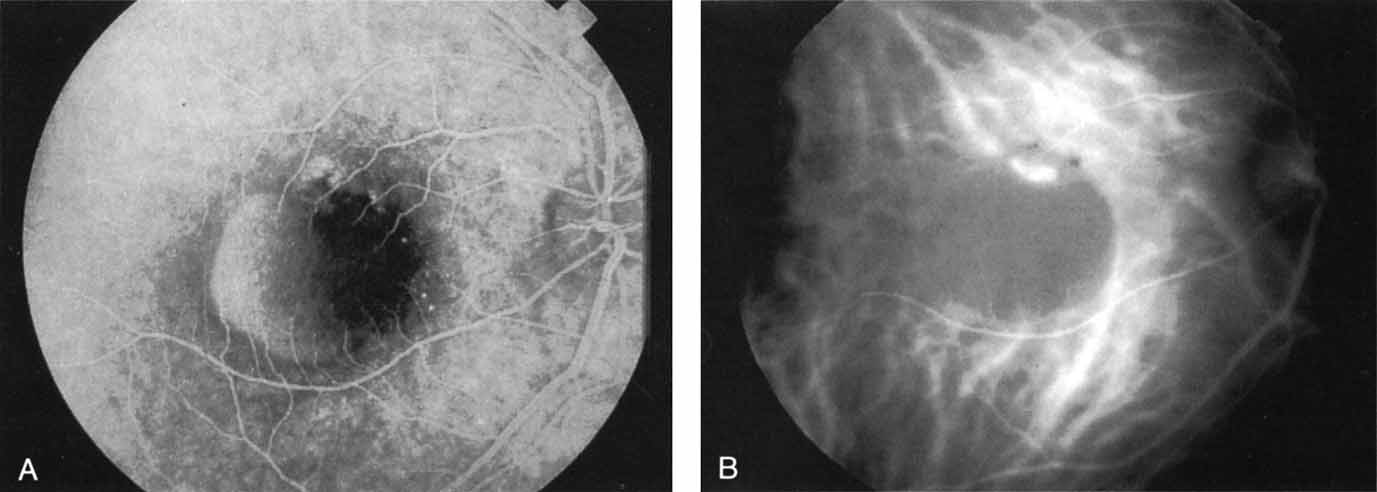

An important report by Chang and co-workers27 lends support to the rationale for interpreting the hyperfluorescence seen on ICG angiography as CNV. In this clinicopathologic study, a patient was identified who had experienced subretinal hemorrhage with early signs of occult CNV on fluorescein angiography (Fig. 4A). Fluorescein angiography demonstrated blocked fluorescence (Fig. 4B). The ICG study, however, demonstrated late staining in a well-circumscribed fashion, which the authors interpreted as a “plaque” of occult CNV (Fig. 4C). When the patient died, this area was evaluated and studied histopathologically and compared with the picture seen on ICG angiography. The area of hyperfluorescence on the ICG study corresponded precisely to a thin layer of fibrovascular tissue beneath the pigment epithelium and neurosensory retina, confirming that the late-staining tissue imaged with ICG angiography was truly a neovascular membrane (Fig. 4D).